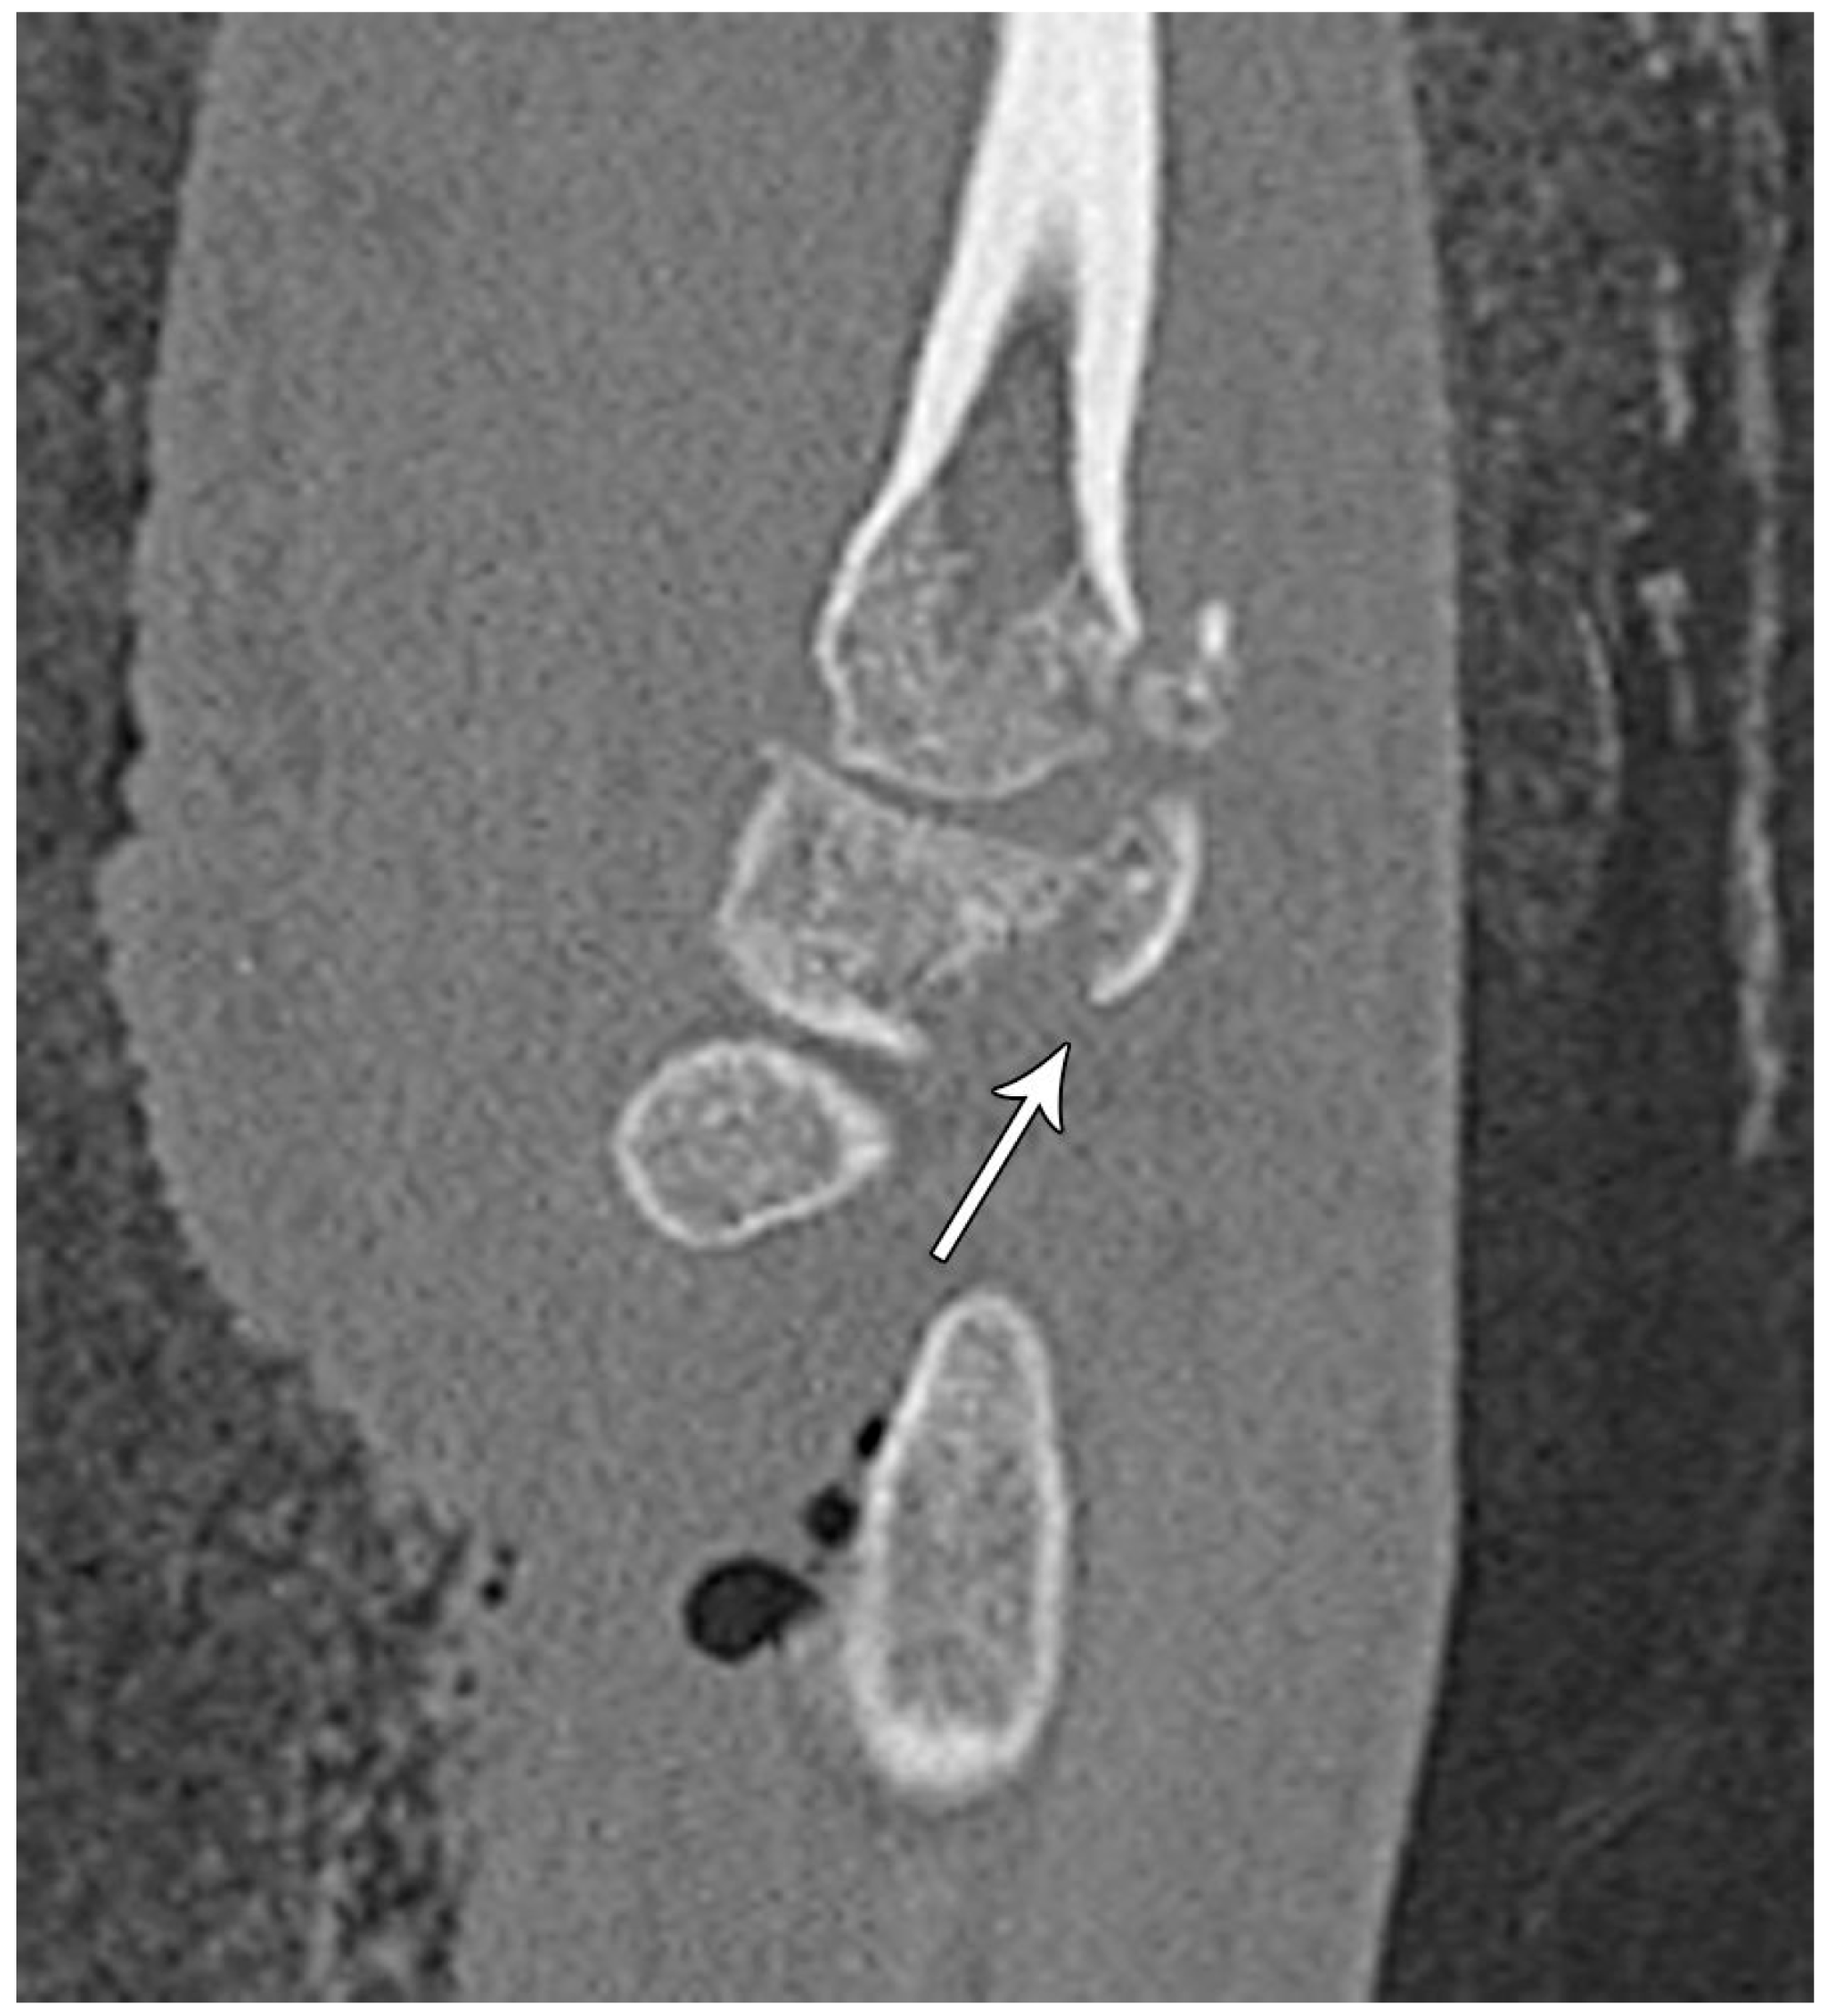

Figure 16. Sagittal reformatted CT of the wrist showing transarticular lunate fracture (arrow).